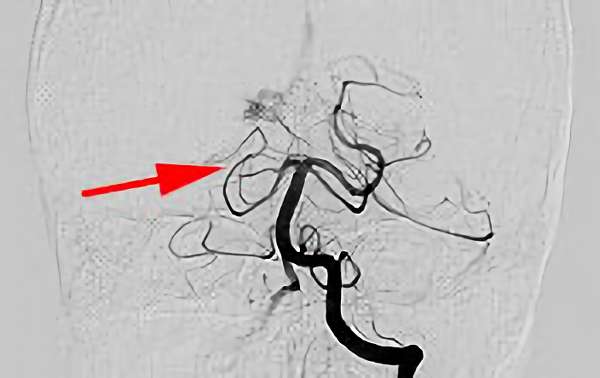

No.1585 手術前